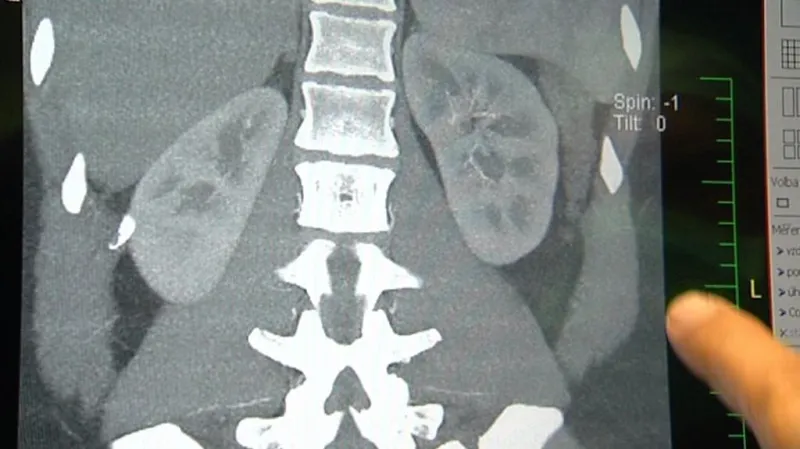

Podle něj jde o velmi náročnou transplantaci, protože ledviny dítěte jsou malé a na velmi jemných cévách. „Tyto ledviny musíte transplantovat tomu dospělému příjemci. Pokud všechno dopadne dobře, tak ty ledviny v tom těle rostou. Nedorostou do běžné velikosti, ale funkci mají výbornou,“ řekl Havránek. Celkem takto centrum transplantovalo 14 ledvin.